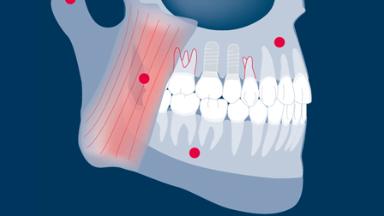

Implantes e suas próteses substituem os dentes. Eles, portanto, têm que participar plenamente da função oral. Uma parte substancial da função oral está relacionada à oclusão quando os dentes e seus substitutos entram em contato. Este módulo examinará a capacidade dos implantes e suas próteses de suportar forças oclusais e oferecer diretrizes para o esquema oclusal.

- reconhecer características de forças oclusais e diferenças biofísicas em como dentes e implantes respondem a eles.

- discutir o impacto potencial das forças oclusais nas complicações e falhas dos implantes e suas próteses.

- aplicar diretrizes recomendadas para o manejo oclusal na terapia com implantes.